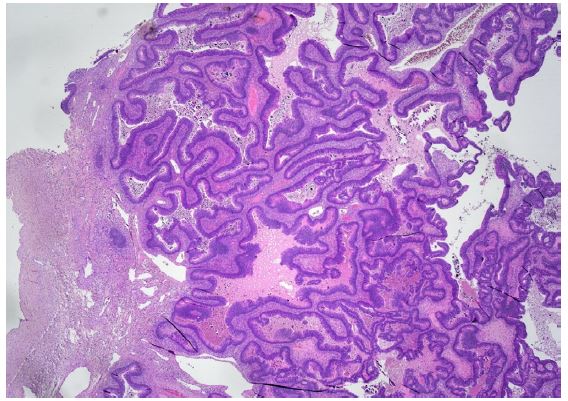

Nevertheless, the patient was assessed by a colorectal Multidisciplinary Team (MDT) at Masaryk Memorial Cancer Institute (MMCI), which decided on adjuvant therapy for the stenotic tumour. Adjuvant chemotherapy on the base of 5 fluorouracil (FU/FA Mayo) was administered. However, this was converted to monotherapy capecitabine due to an allergic skin reaction and neutropenia grade IV. Further therapy was uncomplicated, and close follow-up was recommended. An elevation of tumour marker Carcinoembryonic Antigen (CEA) of 21,8 μg/l was found in October 2017. However, a normal level of the Carbohydrate Antigen (CA) 19-9 of 25.2 ng/ml was noted. Subsequent assessment revealed a left ovarian mass with suspicion of a metastatic process. In November 2017, the patient underwent a gynaecologic evaluation followed by explorative laparotomy at the Department of Gynaecology in the University Hospital Brno. A hysterectomy with bilateral oophorectomy and appendectomy was performed, and malignant ascites was also found. Histological findings showed metastases of moderately differentiated intestinal adenocarcinoma in the left ovary (Figure 1b), identical to the primary transverse colon tumour resected in 2013. KRAS, NRAS and BRAF gene mutations were not detected. The postoperative recovery was uncomplicated, and the patient was referred back to medical oncologists at MMCI. A follow-up Positron Emission Tomography/Computed Tomography (PET/CT) scan was performed in December 2017. It discovered a small metabolically active lesion measuring 12 mm located in the pyloric region closer to the gastric, small curvature (Figure 2). Tumour marker CEA was again slightly elevated (9,4 μg/l) (Figure 3). A gastroduodenoscopy showed prominent gastric walls in the region of the angular notch without mucosal changes. A biopsy was taken, and histologic examination revealed benign atrophic gastritis only (Figure 4).

Figure 1b: Microscopic histological findings. A resected specimen of the sigmoid colon showed an irregular ulcerated lesion. A histological examination of the resected specimen of the sigmoid colon revealed a moderately differentiated adenocarcinoma invading the subserosal layer. (×100 magnification; haematoxylin and eosin stain).